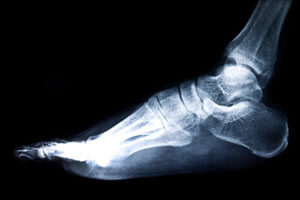

Диагностика

Пренебрежения собственным здоровьем могут серьезно усугубить состояния, привести к неправильным срастаниям или воспалительным заболеваниям костей.

Чтобы точно определить диагноз, врач-травматолог осматривает поврежденную конечность, подробно расспрашивает пациента о способе получения травмы. Поставить точный диагноз и определить место перелома помогает рентгенография в 2 разных плоскостях.